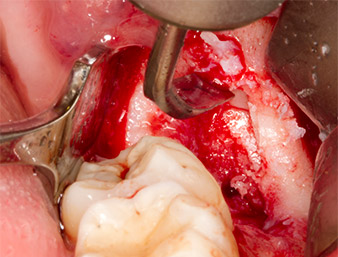

Tras una anestesia local y por conducción, el campo quirúrgico se abrió mediante los tejidos blandos para tener un acceso bucal-retromolar y se dejó expuesto (figura 3).

El tejido situado por encima del resto radicular no se había osificado por completo y constaba en su mayor parte de un tejido granulado con alteraciones inflamatorias (figura 4).

tejido granulado

Imagen 4: Dos ganchos de Langenbeck y un raspador según Prichard exponen el campo quirúrgico. Se distingue un tejido granulado de la primera osteotomía que no ha cicatrizado en su totalidad.